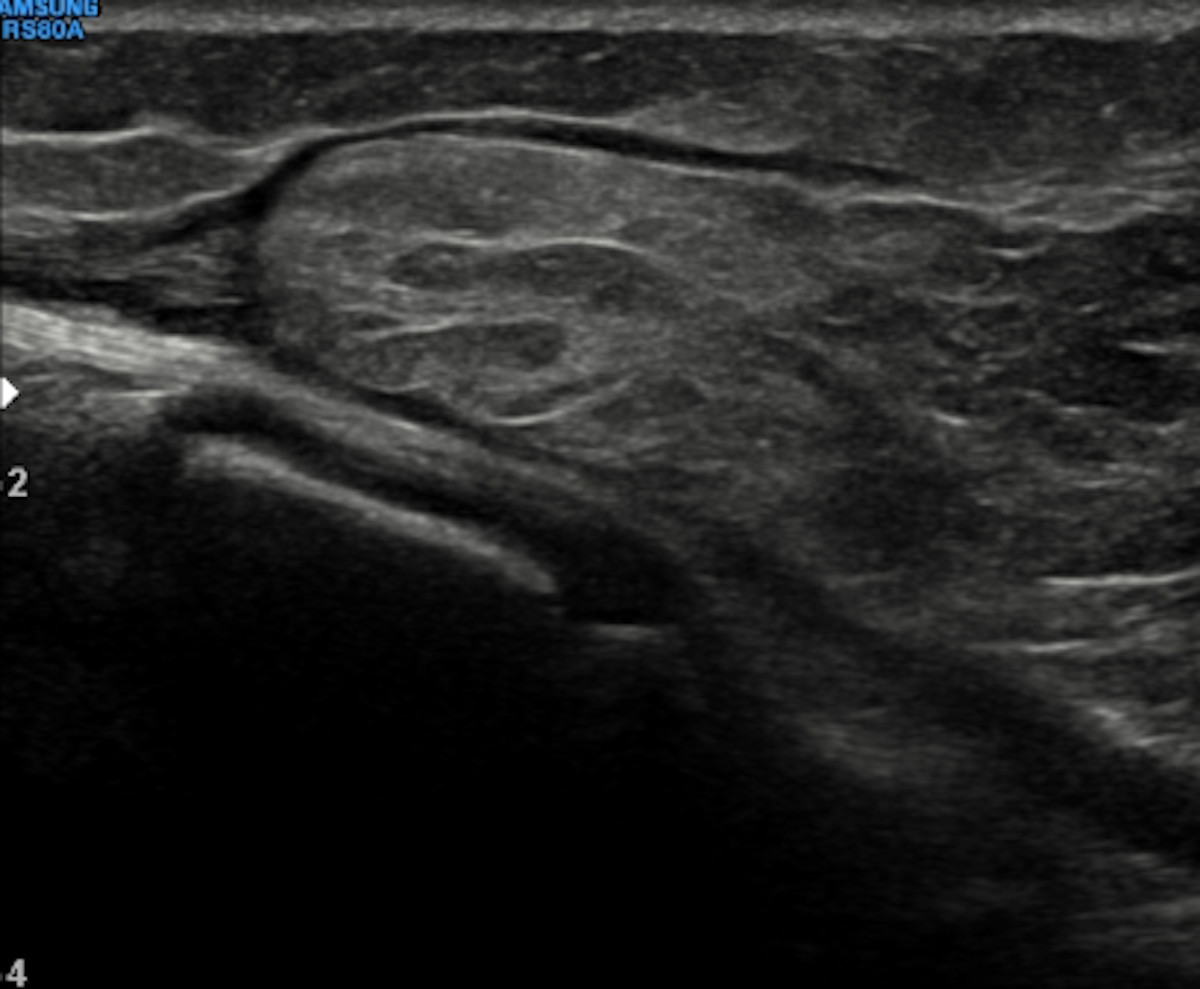

Fig. 1. Ecografía de partes blandas: lesión subcutánea de 20 x 78 mm, ecogénica de morfología fusiforme, con bordes bien definidos y halo anecoico sin señal Doppler color.